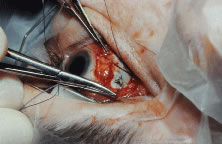

RECESSION PROCEDURE: LIMBAL APPROACH

Two 6-0 silk stay sutures are passed through the conjunctiva and superficial scleral tissue at the limbus (see Fig. 49). These sutures are used to stabilize the globe during the procedure. These stabilizing sutures attached to bulldog clamps will hold the globe in adduction or abduction as required.

A no. 15 surgical knife or other similar instrument is used to penetrate the conjunctiva at the limbus (Fig. 50). Care is taken to approach the limbustangential to the globe so that inadvertent penetration of the sclera or cornea is avoided. A Westcott scissors also may be used to incise the conjunctiva at the limbus. To facilitate this step, conjunctiva is lifted gently with a 0.5-mm Castroviejo forceps (see Fig. 50).

|

A blunt-tipped Westcott scissors is used to extend the incision for about 3 clock hours (Fig. 51). Once the fused area of conjunctiva and anterior Tenon's capsule has been penetrated, blunt dissection is performed to carry the limbal incision back toward the muscle. This maneuver is best accomplished by directing the closed tips of a blunt-tipped Westcott scissors into the tissue and letting them open to spread the tissue in a plane between the scleral surface and the underside of Tenon's tissue. The limbal incision is extended radially with a Westcott scissors (Fig. 52). Care is taken to avoid cutting into the anterior portion of the rectus muscle insertion (Fig. 53).

|

|

Figure 54 shows the conjunctiva being elevated by the assistant with Castroviejo forceps. The anterior extension of the muscle can be seen.

|

A Jameson hook is passed under the rectus muscle about 2 mm posterior to the insertion (Fig. 55). The insertion has been identified previously with a Stevens' hook that is used to lift up the tendon to facilitate passage of the Jameson hook.

Figure 56 shows sharp dissection of the intermuscular septa and the check ligaments that extend from the orbital surface of the muscle. The assistant applies gentle traction to the conjunctiva to show the surgeon the weblike bands that are to be cut. Care is taken not to penetrate the muscle capsule because penetration can injure the muscle and will cause bleeding. This dissection is carried back about 4 to 5 mm for recessions and 5 to 9 mm for resections.

A single-armed 6-0 synthetic absorbable suture is passed through the muscle tendon near its insertion (Fig. 57). A double-lock bite is taken with the needle, and the suture is tied with two square knots to secure it to the upper and lower poles of the tendon of the rectus muscle. The muscle is lifted or tented off of the surface of the globe with a Jameson hook. A Westcott scissors is used to cut the muscle free (Fig. 58).

|

|

The assistant holds the Castroviejo caliper that marks the location of the new insertion (Fig. 59). Care is taken to locate it directly posterior to the stump of the old insertion and to avoid inadvertent supraplacement or infraplacement of the new insertion.

|

An intrascleral passage of the needle is used to secure the muscle to the globe (Fig. 60). The intrascleral bites are usually 3 to 4 mm in length. The superior and inferior pole sutures are tied to secure the muscle to its new insertion site (Fig. 61), and the wound is inspected. The new insertion is measured to ensure that the appropriate amount of recession effect has been achieved. The sutures are trimmed, and the conjunctiva is brought back to the limbus (Fig. 62). Care is taken to identify the conjunctival tissue. Confusion may occur when an attempt is made to differentiate this tissue from Tenon's tissue. A fine absorbable suture such as 8-0 collagen is used to secure the conjunctiva at the limbus (Fig. 63). If an en bloc recession technique is used, or a bare sclera closure is required, the conjunctiva is recessed 4 to 5 mm back from the limbus, leaving the sclera between the anterior conjunctiva edge and the limbus uncovered. This technique is useful when conjunctival and subconjunctival tissue is contracted or when it restricts movement of the globe.